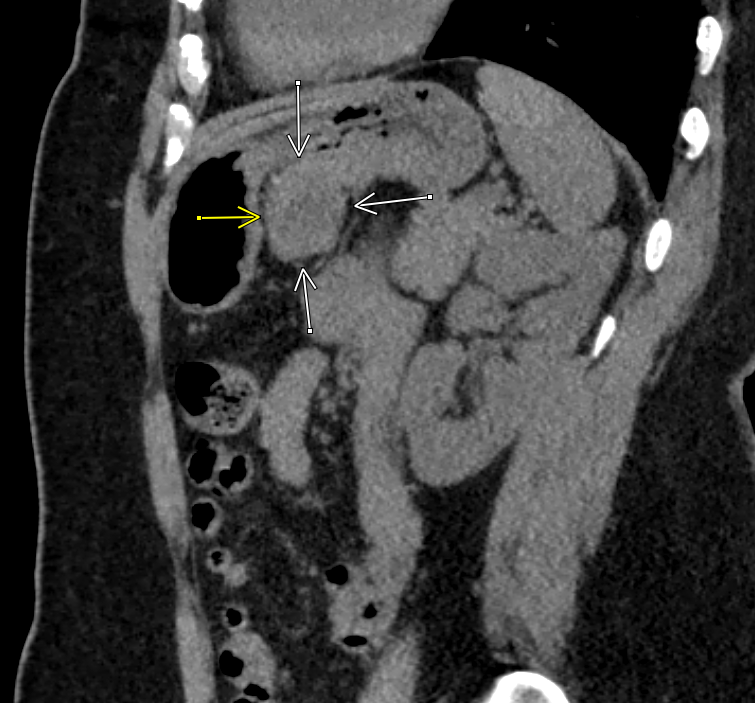

#radres sometimes the finding is in the bottom corner, outside the requested area#easytomiss T4#fracture on a cervical#spine CT#FOAMed#FOAMrad#EMrad#MSKrad#Neurorad@ASER_ERad@NASSspinepic.twitter.com/zYOqyGSaFl